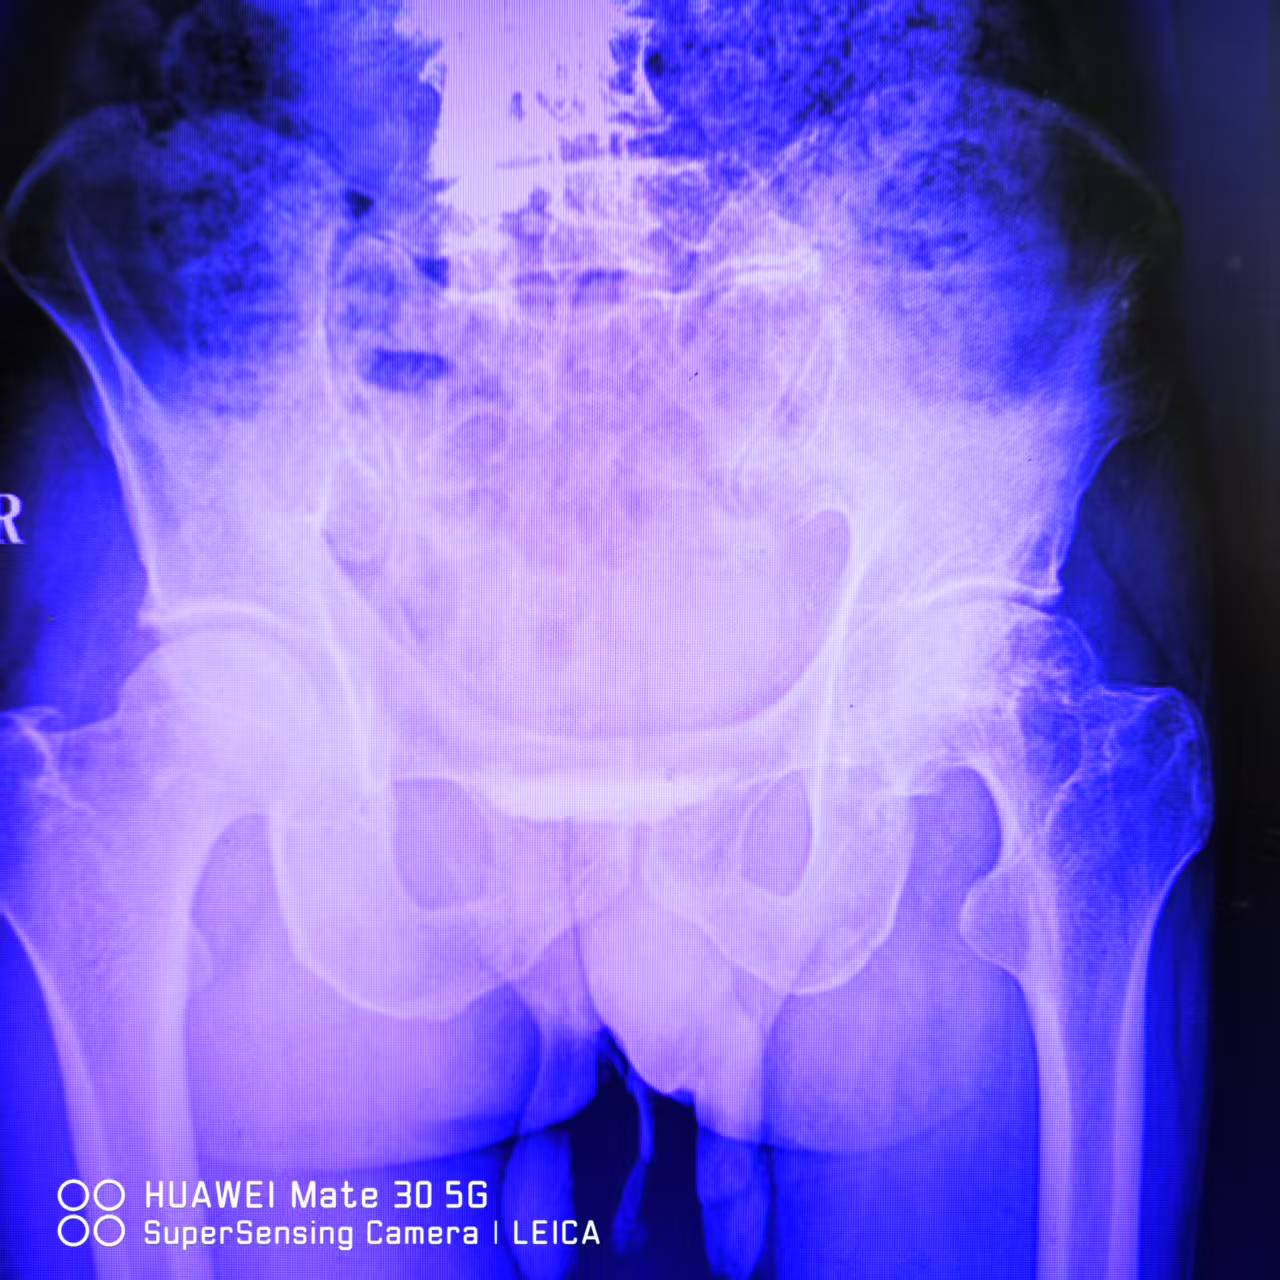

全髋关节置换术

患者为老年男性,诊断为‌双侧股骨头缺血性坏死‌,左侧病变较严重。